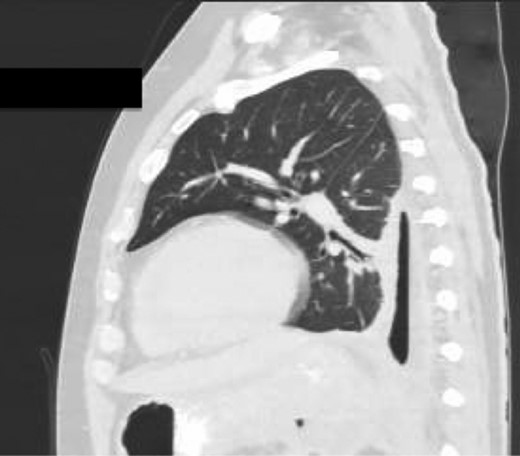

Chest X-ray in ICU following drainage showed what was thought to be Pneumomediastinum (Figs 1 and 2), and given this concern he was referred to the Cardiothoracic service. Subsequent CT suggested a large loculated hydro-pneumothorax, which in retrospect represented the drained Pseudocyst communicating through the diaphragm (Figs 3 and 4).

Area of communication between the drained Pseudocyst and the Left Pleura. Space noted with arrow.